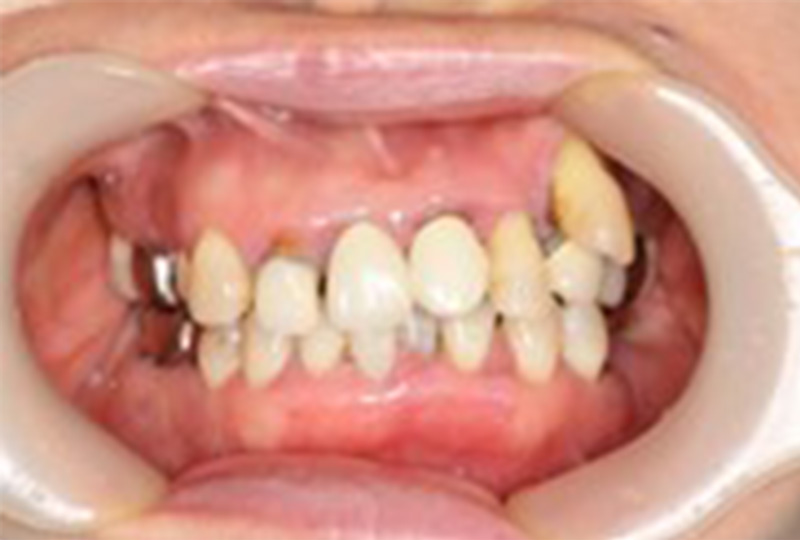

当院では、基本となる保険診療だけでなく、より高水準な「自由診療」も行っています。

審美性にこだわった治療から保存が難しいと言われた歯の保存やお口全体をより良い状態にする一歩進んだ専門的な治療を行います。